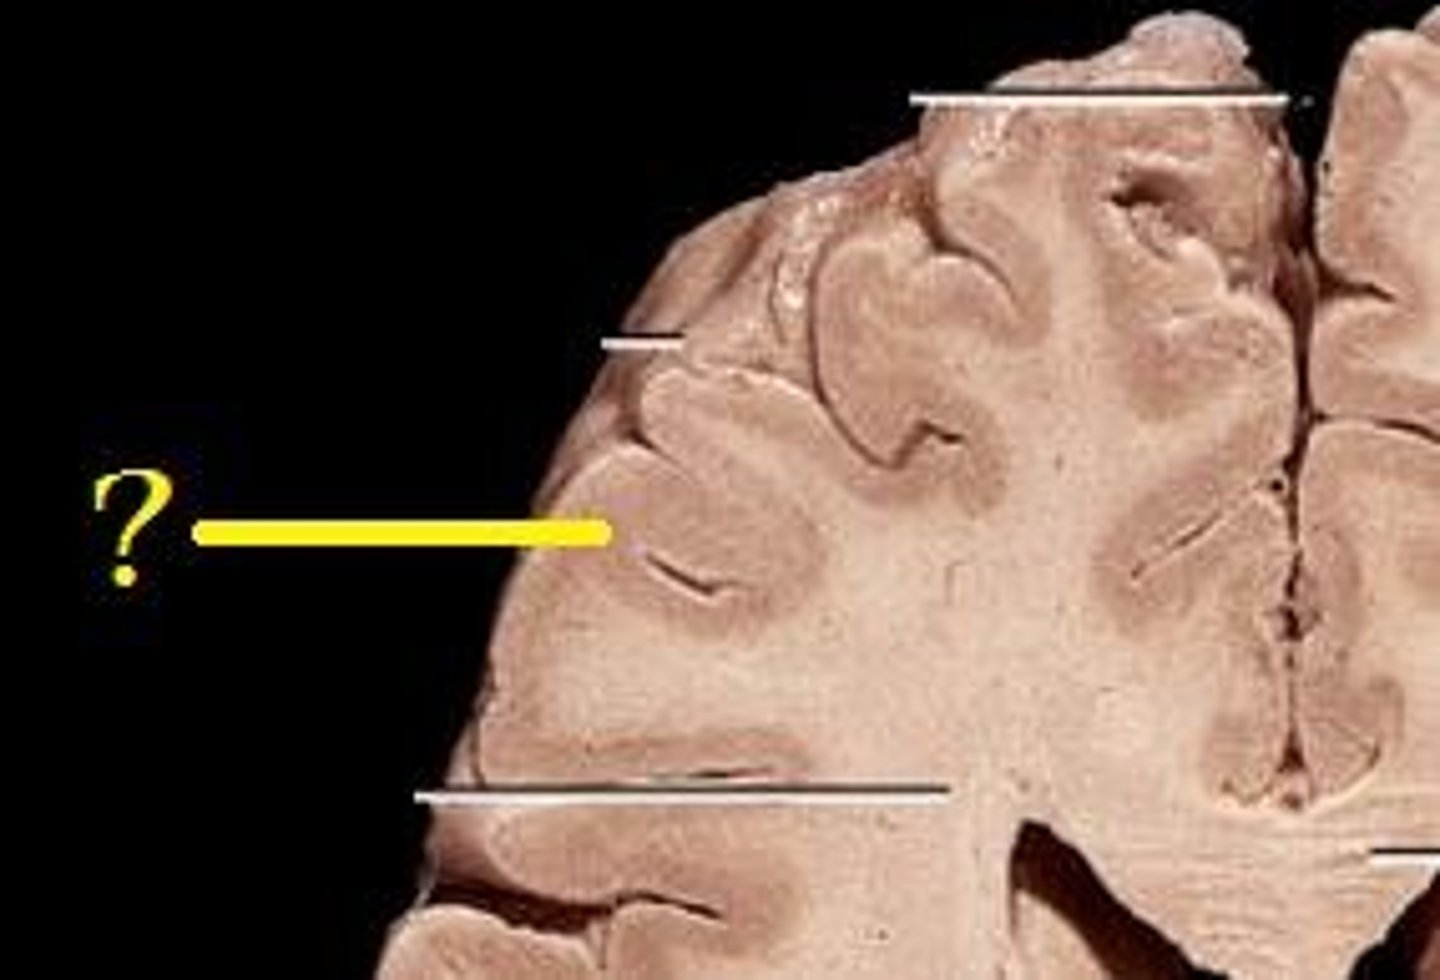

Cerebral Cortex (surface)

Cerebral White matter

Choroid Plexus